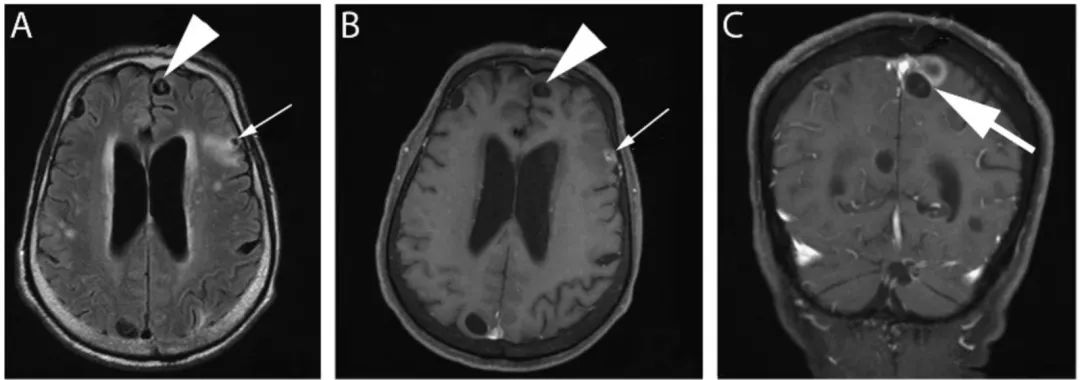

图20 脑囊虫病

轴位FLAIR(A)、增强T1IW像 (B)和冠状位增强T1WI(C)显示不同时期脑囊虫病的多发囊性病灶。囊泡期可见左额叶前部薄壁囊肿,囊内物质在FLAIR为低信号,无明显增强(楔形箭头);背外侧左额叶囊肿FLAIR高信号、增强后高信号(细箭头),为胶囊囊泡或神经囊尾蚴的颗粒状结节阶段。(C)上矢状窦相邻的两个囊肿(粗箭头)。